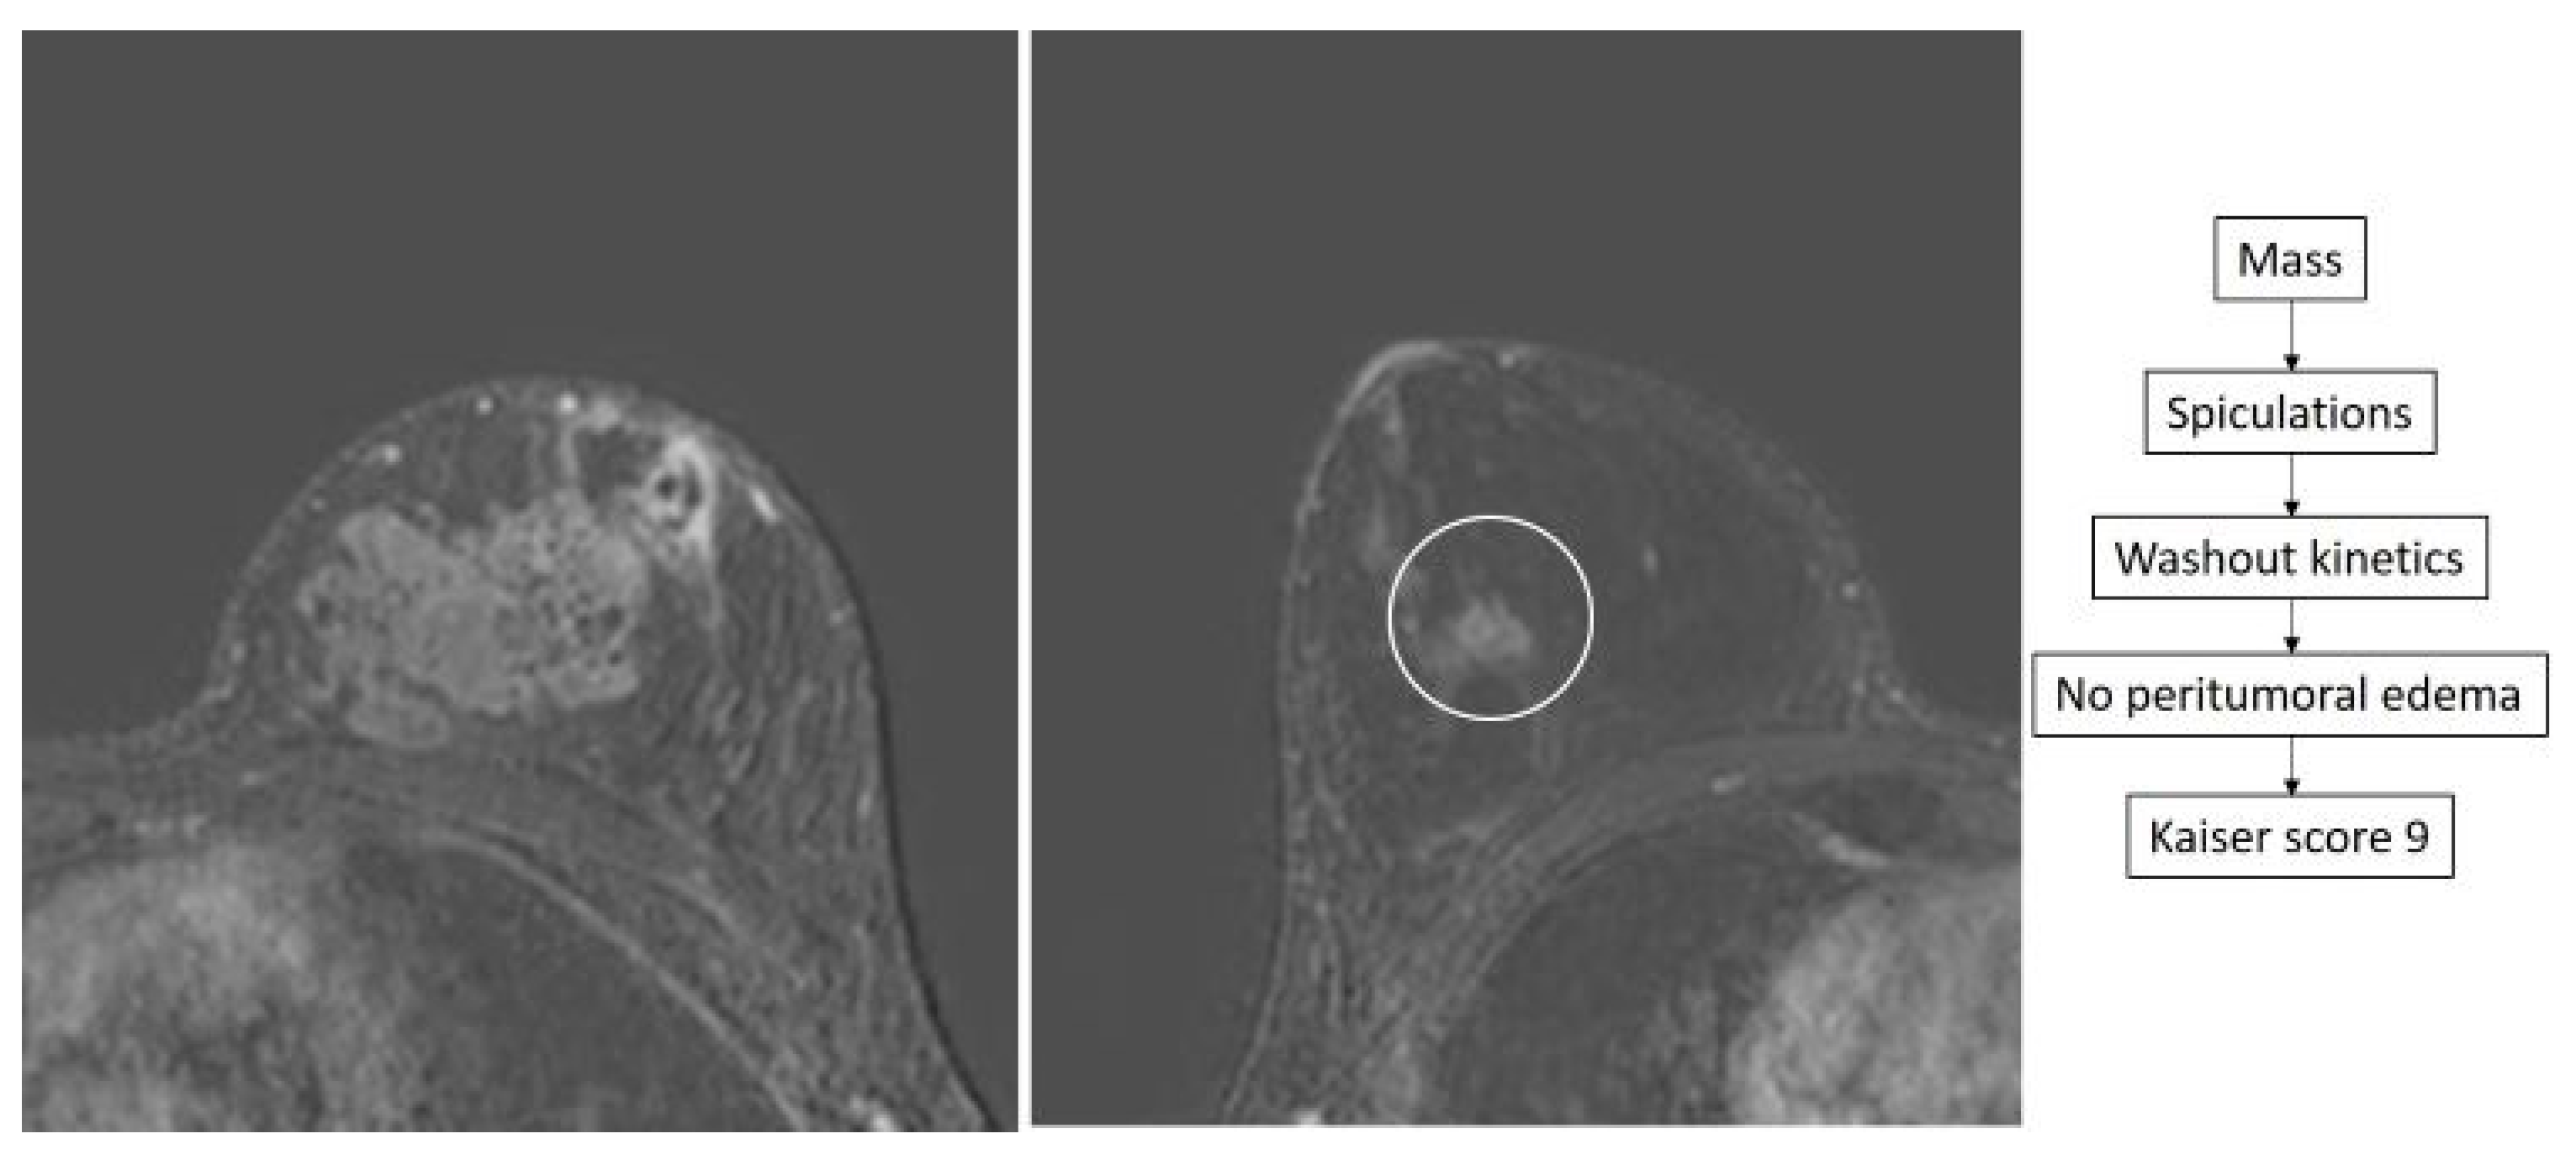

- Dietzel, M.; Baltzer, P.A.T. How to Use the Kaiser Score as a Clinical Decision Rule for Diagnosis in Multiparametric Breast MRI: A Pictorial Essay. Insights Imaging 2018, 9, 325–335. [Google Scholar] [CrossRef] [PubMed]

- Baltzer, P.A.T.; Krug, K.B.; Dietzel, M. Evidence-Based and Structured Diagnosis in Breast MRI Using the Kaiser Score. ROFO. Fortschr. Geb. Rontgenstr. Nuklearmed. 2022, 194, 1216–1228. [Google Scholar] [CrossRef]